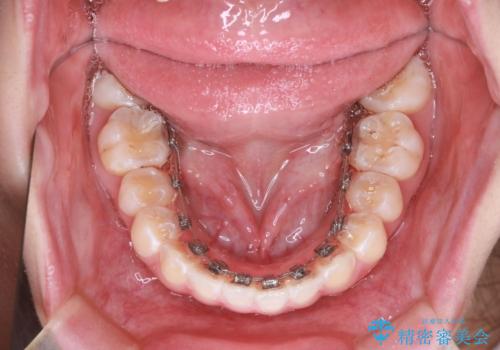

「フルリンガル矯正|アンカースクリューを活用し正中を整えた症例」

- 治療計画

矯正装置を装着し、アンカースクリューを活用しながら奥歯を少しずつ後ろへ動かし、正中を整えていきました。治療には時間がかかりましたが、計画通りに歯を移動させ、バランスの取れた歯並びへと仕上げることができました。裏側矯正のため、見た目を気にすることなく治療を進められた点も、患者様にとって大きなメリットでした。治療後は、「正中がしっかり合って、口元がスッキリした」とご満足いただきました。